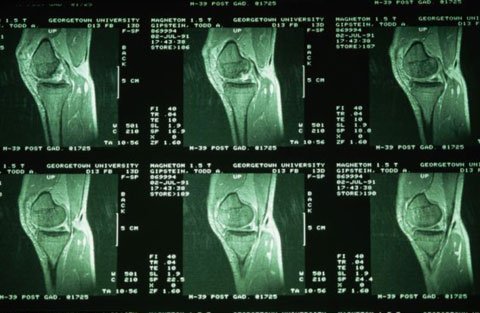

Kết quả chụp MRI cho thấy, hình dạng xương bánh chè ở đầu gối của mỗi người là độc nhất vô nhị. Ảnh: Corbis |

Một nhóm nghiên cứu Mỹ phát hiện, các xương bánh chè ở đầu gối của mỗi người là độc nhất vô nhị. Chúng có thể mang tới một phương pháp mới nhằm nhận dạng người ở các sân bay hoặc những chốt kiểm tra an ninh khác.

Các nhà nghiên cứu cho hay, hàng loạt thử nghiệm ban đầu với hệ thống chụp cộng hưởng từ (MRI) xương bánh chè ở đầu gối đạt độ chính xác tới 93%.